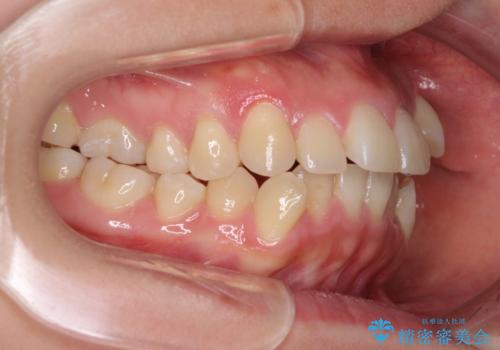

また、八重歯により上顎奥歯が前方に位置しており、咬み合わせの改善も必要な状況でした。

インビザラインによる矯正治療を希望されたため、上顎歯列の側方拡大奥歯の遠心移動のための補助装置を併用し、その後はインビザラインにて行うこととしました。

八重歯の動きが鈍く、治療期間は長期化しました。

癒着の疑いもありましたが、アンカースクリューを多用し、何とか改善することができました。